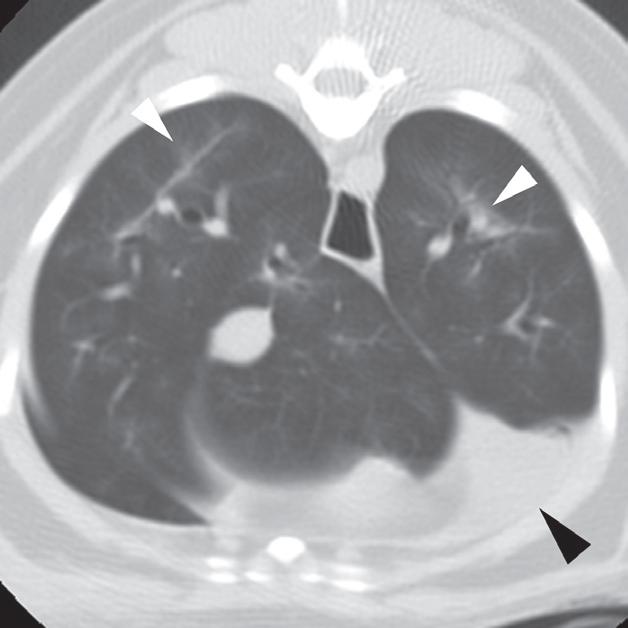

Rycina 4.6.4. Kardiogenny obrzęk płucny (kot) TK

Badanie wykonano u 4-letniej, kastrowanej samicy kota domowego krótkowłosego dializowanej z powodu niewydolności nerek. U pacjentki obserwowano echokardiograficzne objawy łagodnej kardiomiopatii. W momencie wykonywania tomografii komputerowej kot był umiarkowanie przeciążony płynami. Obraz na ryc. a jest reprezentatywnym obrazem na poziomie tylnej części klatki piersiowej, a obrazy przedstawione na ryc. b i c stanowią powiększenie ryc. a. Niewielka objętość płynu opłucnowego unosi powietrzne płuco (a – czarna strzałka). Widoczny jest łagodny, rozproszony wzrost atenuacji płuc z dodatkowymi, licznymi zmianami w typie matowej szyby. Wydaje się, że te ostatnie nacieki są najbardziej widoczne wokół naczyń płucnych (a–c – białe strzałki). Badanie pośmiertne potwierdziło, że nacieki były spowodowane obrzękiem płuc. W tym przypadku obrzęk prawdopodobnie był wynikiem względnej niewydolności komór serca spowodowanej kardiomiopatią i przeciążeniem płynami